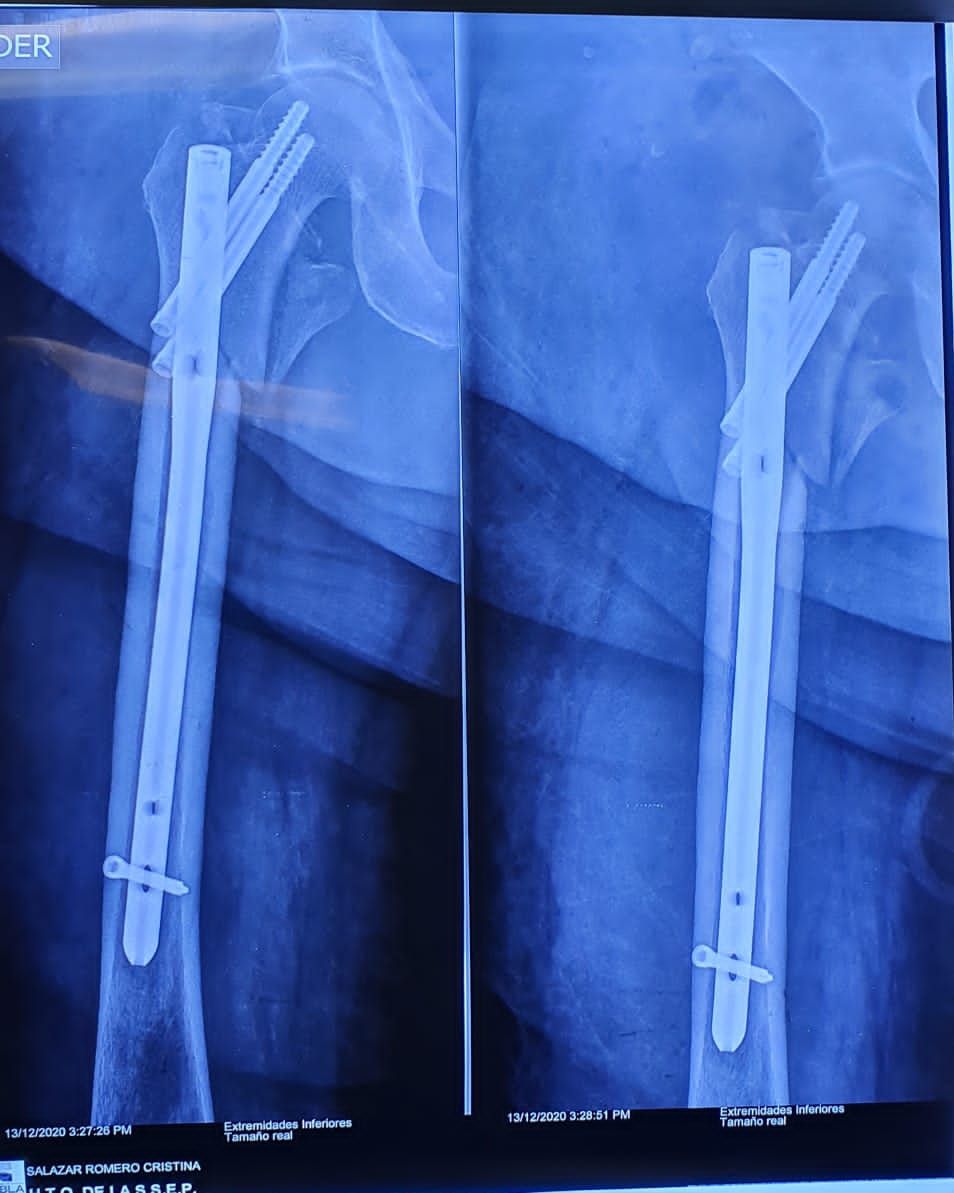

• Fractura de fémur

• Fracturas de cadera

Reparación de fractura de fémur Sin especificar